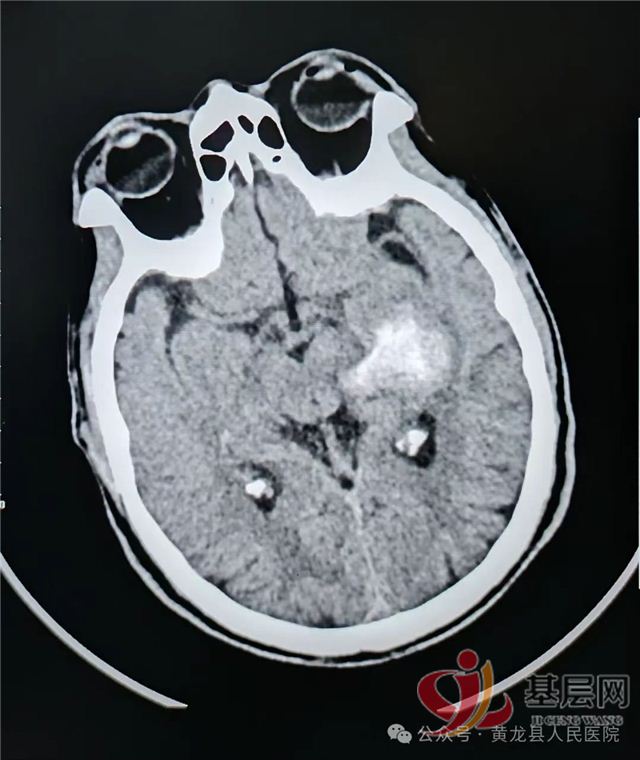

春节收假第一天,黄龙县人民医院外科收治一位72岁,脑出血昏迷患者。因“右侧肢体活动无力3小时,意识不清1小时”,由我院120接诊入院。到院后立即开通绿色通道,完善颅脑CT提示:左侧内囊--丘脑区脑出血,出血量约11ml。给予降颅压、止血后,复查颅脑CT,提示:左侧内囊--丘脑区脑出血增多,出血量约40ml,并破入脑室。

左侧内囊--丘脑区脑出血(约11ml)

术前CT:左侧内囊--丘脑区脑出血破入脑室,出血量巨大,同侧大脑半球受压明显,脑室挤压,中线偏移